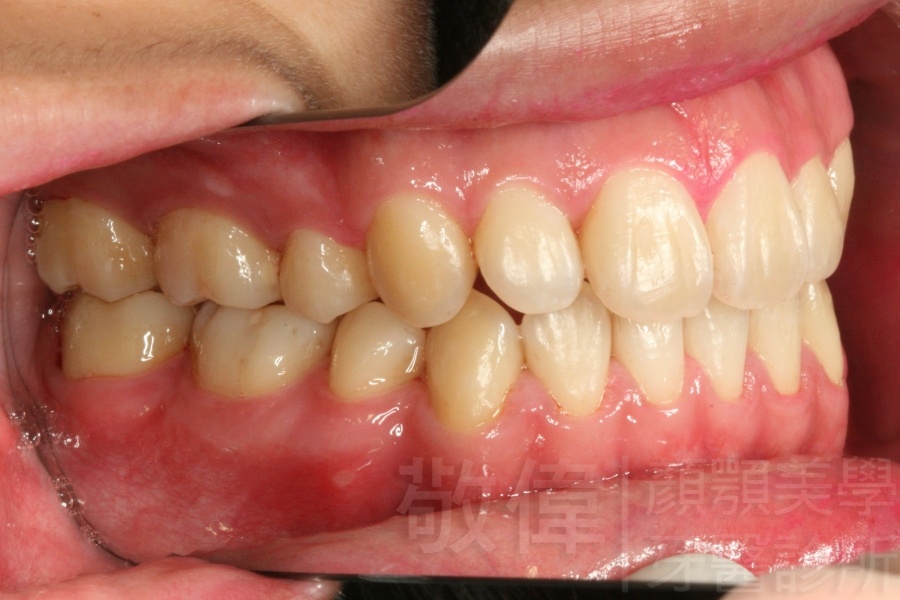

齒顏矯正/戽斗、亂牙、爛牙,變身 免植牙的健牙美女

變臉矯正,原來戽斗妹跟大歪臉變成自信正妹

經由本院3D數影X光影像儀分析、與3D齒顎顏矯正技術,再配合口腔顎面正顎專科醫師施以正顎手術治療,雙方共同合作,使患者臉部外觀有很好的改善,大歪變小歪,產生了天南地北的大改變,她的人生也整個變得不一樣。

因為矯正與正顎手術的配合,使「戽斗妹」變成了「陽光正妹」,完全的改變了她的人生,在面對各種場合、與人交際都散發出自信微笑。所以,奉勸家長,如果小朋友有臉顎畸型的問題,應該考慮配合做這種簡單、安全、有效的正顎手術。